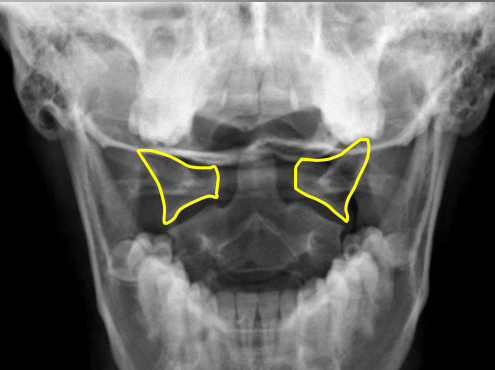

yellow

Occipital condyles

blue

Foramen magnum